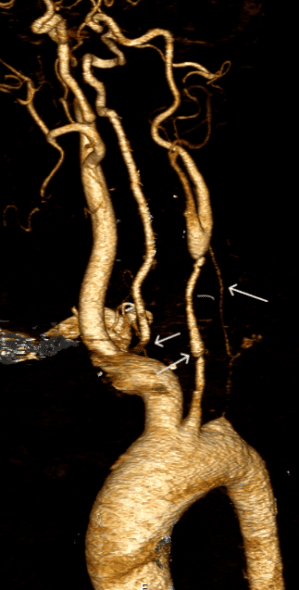

Resim. 30 yaşında takayasu bulunan kadın hastanın beyin ve kola giden damarlardaki tutulumu

Hastalığa bağlı olarak çıkan aortada daha fazla olmak üzere dilatasyon veya anevrizma gelişebilmektedir.